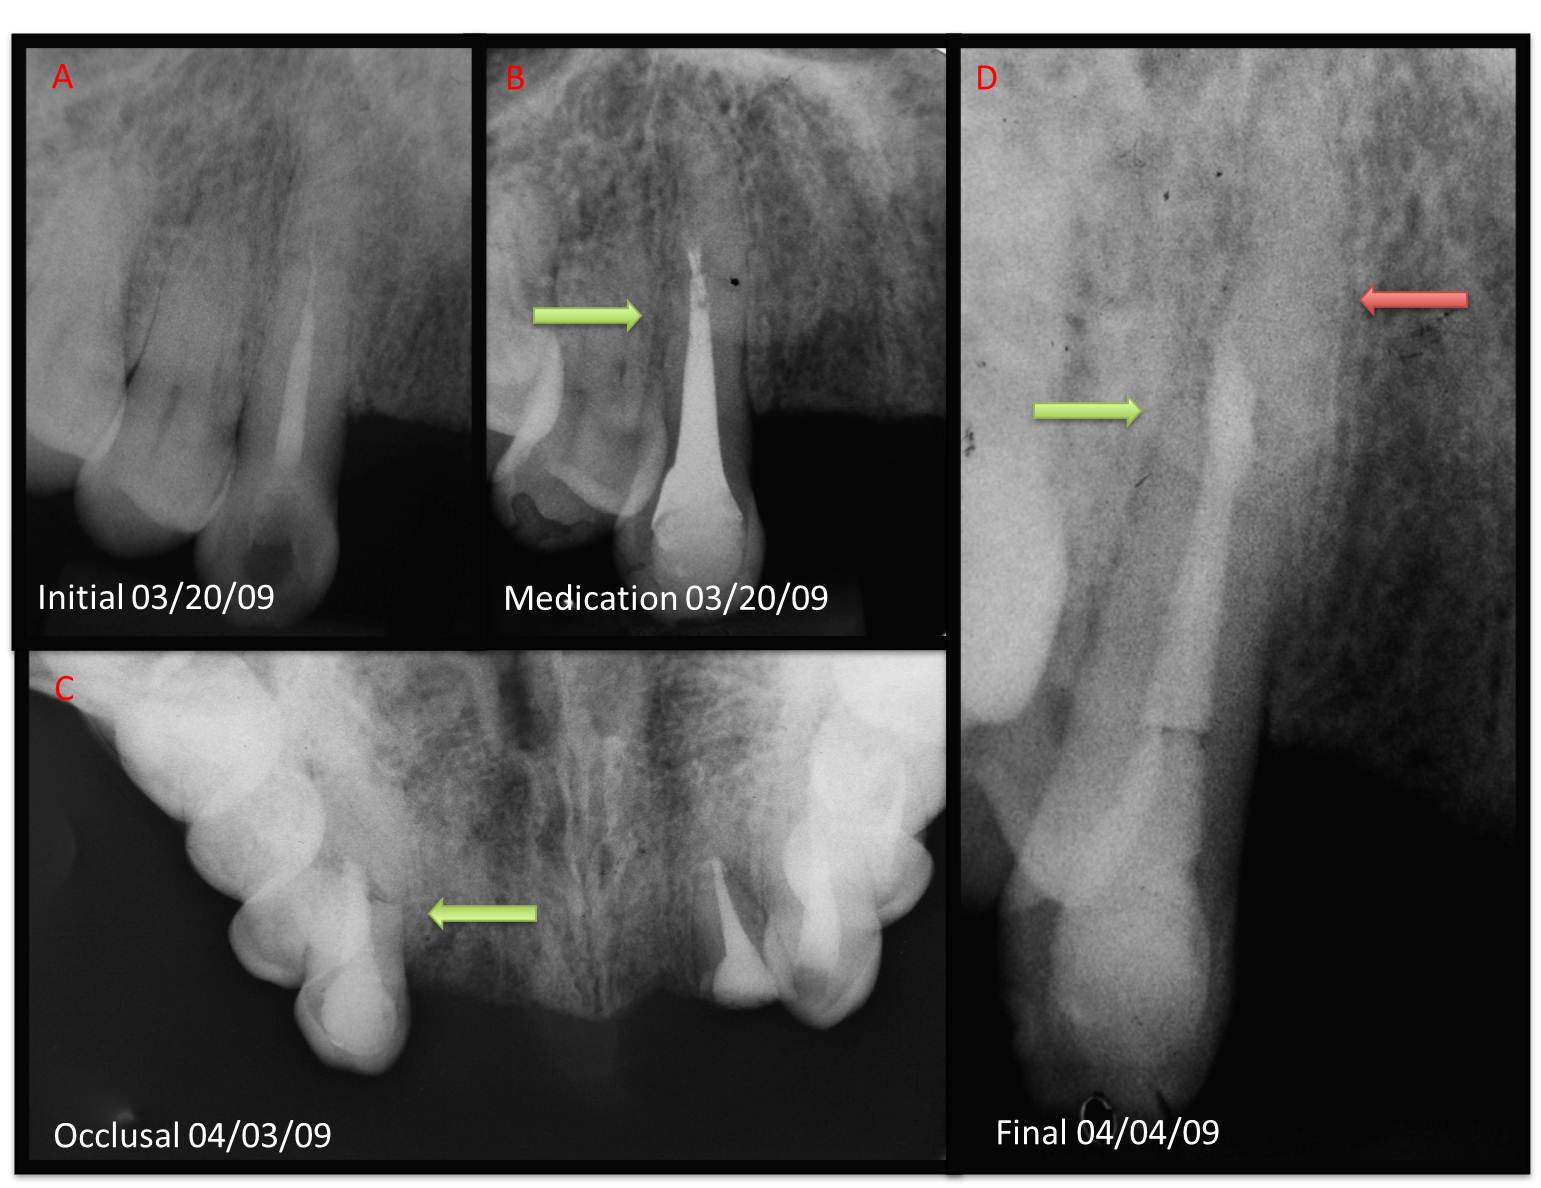

Introduction: The aim of this case report is todemonstrate the retreatment of a maxillary caninediagnosed with a horizontal root fracture utilizingan electronic apex locator and monitored with conebeam computed tomography. Case Report: A 35year old African American male was referred for rootcanal retreatment of a maxillary right canine prior toprosthetic rehabilitation. Following removal of guttapercha, an apex locator was utilized to determine thelength of the root canal. After a more comprehensivedental history, the patient confirmed a previouslyunreported history of dental trauma at this time,leading to the suspicion of a horizontal root fracture.Clinical microscopy detected a connective tissue in theapical third of the root canal and multiple periapicaland occlusal radiographs enhanced visualizationof a horizontal root fracture. The coronal segmentwas filled with an MTA apical plug and the apicalsegment remained stable. A recall after 1.5 yearswas performed with CBCT, which showed no apicalradiolucency. Discussion: The present case reportreinforces the precept that detailed dental history andcareful observation of radiographs are critical factorsfor obtaining an accurate diagnosis. Fundamentaladjuncts, such as microscopy, apex locators andCBCT imaging, can potentially aid in the diagnosisand the subsequent treatment plan of horizontal rootfracture.